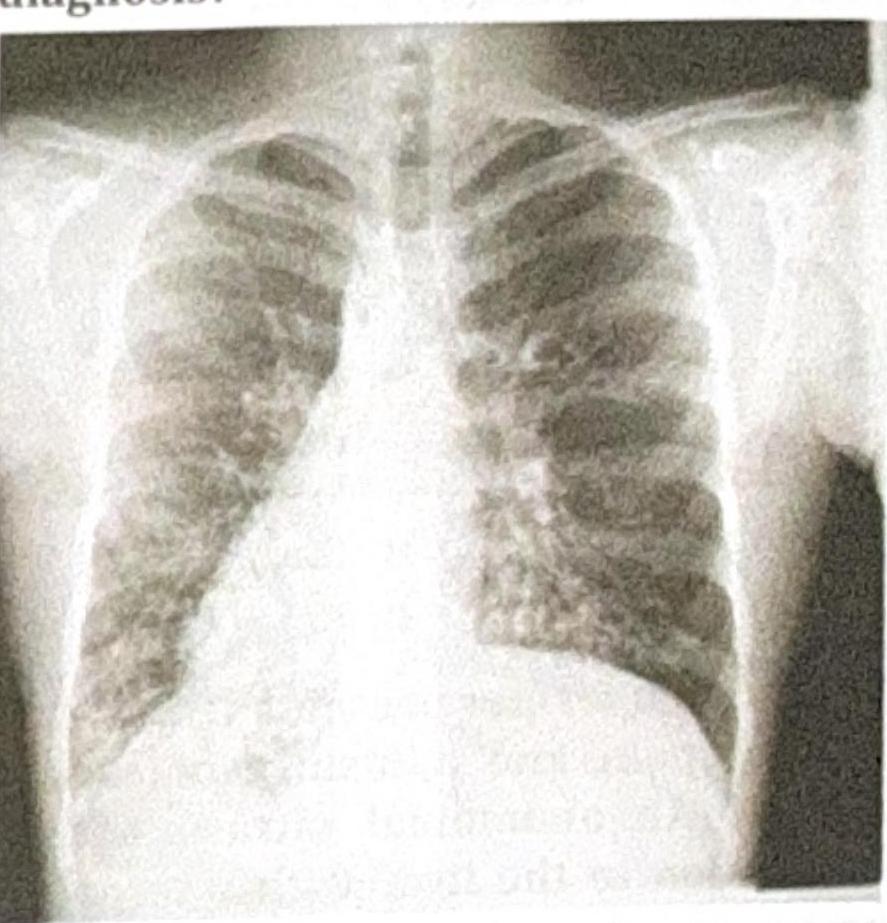

A patient presents with recurrent lung infections, and the chest X-ray provided shows a characteristic finding. What is the most likely diagnosis?

Explanation: ***Kartagener syndrome*** - This syndrome is a subgroup of **primary ciliary dyskinesia** and is characterized by the triad of **situs inversus** (dextrocardia as seen on the chest X-ray), **chronic sinusitis**, and **bronchiectasis**. - Recurrent lung infections are a common presentation due to impaired mucociliary clearance leading to bronchiectasis. *Cystic fibrosis* - While cystic fibrosis does present with **recurrent lung infections** and **bronchiectasis**, it is not typically associated with **situs inversus** or other malformations of organ placement. - Diagnosis is usually supported by a **positive sweat chloride test** and genetic testing for CFTR mutations. *DiGeorge syndrome* - This syndrome is characterized by **T-cell immunodeficiency**, **hypocalcemia**, and **congenital heart defects**. - Recurrent infections in DiGeorge syndrome are due to immunodeficiency, not primarily due to impaired ciliary function or situs inversus. *Down syndrome* - Down syndrome is a chromosomal disorder associated with intellectual disability, distinctive facial features, and an increased risk of several health problems, including **congenital heart disease** and **immune dysfunction**. - Recurrent lung infections can occur due to weakened immune function or structural airway abnormalities, but it does not cause situs inversus or primary ciliary dyskinesia.

Explanation: ***Miliary TB*** - The chest X-ray shows diffuse, small, uniformly distributed nodular opacities (2-3 mm in diameter) bilaterally, characteristic of "**millet seed**" pattern seen in **miliary tuberculosis**. - This pattern results from the hematogenous spread of *Mycobacterium tuberculosis* throughout the lungs, often presenting with **low-grade fever** and constitutional symptoms. *ILD* - **Interstitial lung disease (ILD)** typically shows reticular, nodular, or ground-glass opacities, sometimes with honeycombing, but the pattern is usually more heterogeneous and often basal or peripheral, unlike the uniform fine nodularity seen here. - While some ILDs can present with diffuse nodular patterns, the clinical context of **fever** and the classic "millet seed" appearance are more indicative of miliary TB. *Bronchopneumonia* - **Bronchopneumonia** presents as patchy, often ill-defined, multifocal areas of opacification or consolidation, usually distributed around the bronchi. - It does not typically cause the fine, diffuse, and uniform nodular pattern seen in this image, which represents widespread interstitial or alveolar involvement rather than primarily bronchial inflammation. *Consolidation* - **Consolidation** appears as a homogeneous opacification that obliterates vessels and airway walls, often with air bronchograms, typically confined to a lobe or segment. - The image shows diffuse nodular infiltrates rather than large, confluent areas of homogeneous opacification, making isolated consolidation an unlikely primary description.